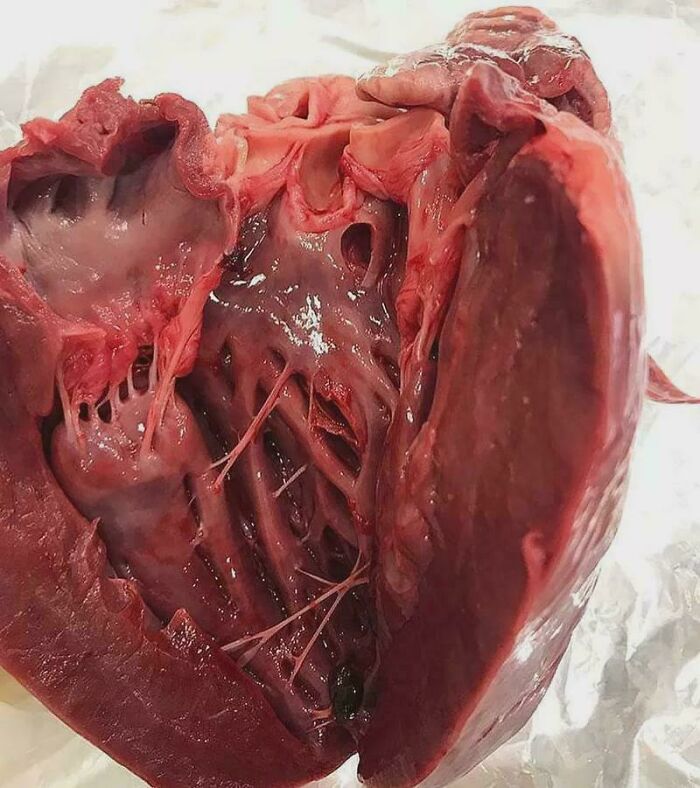

Hypertrophic Cardiomyopathy

This is a condition in which the heart muscle becomes thick, especially of the ventricles, which is seen very clearly in this picture.

The average left ventricular wall thickness in normal adults is 1.1 cm, but there are exceptions. Trained athletes have hearts that have left ventricular mass up to 60% greater than untrained subjects, with an average left ventricular wall thickness of 1.3 cm...